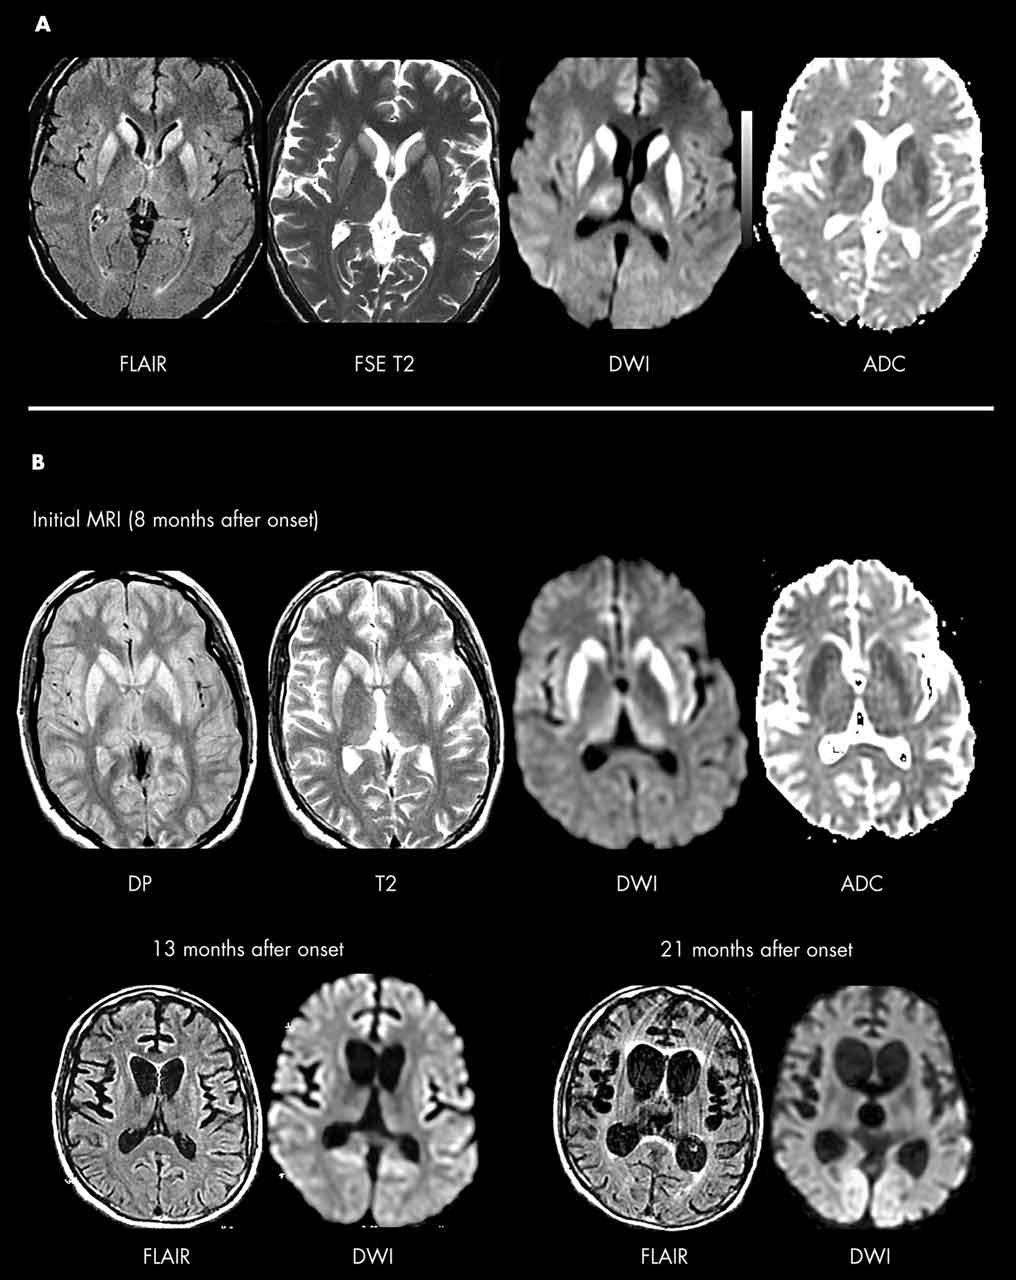

Creutzfeldt-jakob Disease

Creutzfeldt-Jakob Disease (CJD) is a rare, rapidly progressive, fatal, degenerative disorder of the central nervous system. Death often occurs within six to 12 months from the onset of symptoms; however, in ... Access This Document

Creutzfeldt Jakob disease (CJD) was first described by Creutzfeldt and Jakob in the early 1920s. This disease occurs worldwide at a very low rate. It is one of a group of sub-acute degenerative diseases of the brain caused by prions. ... View Doc